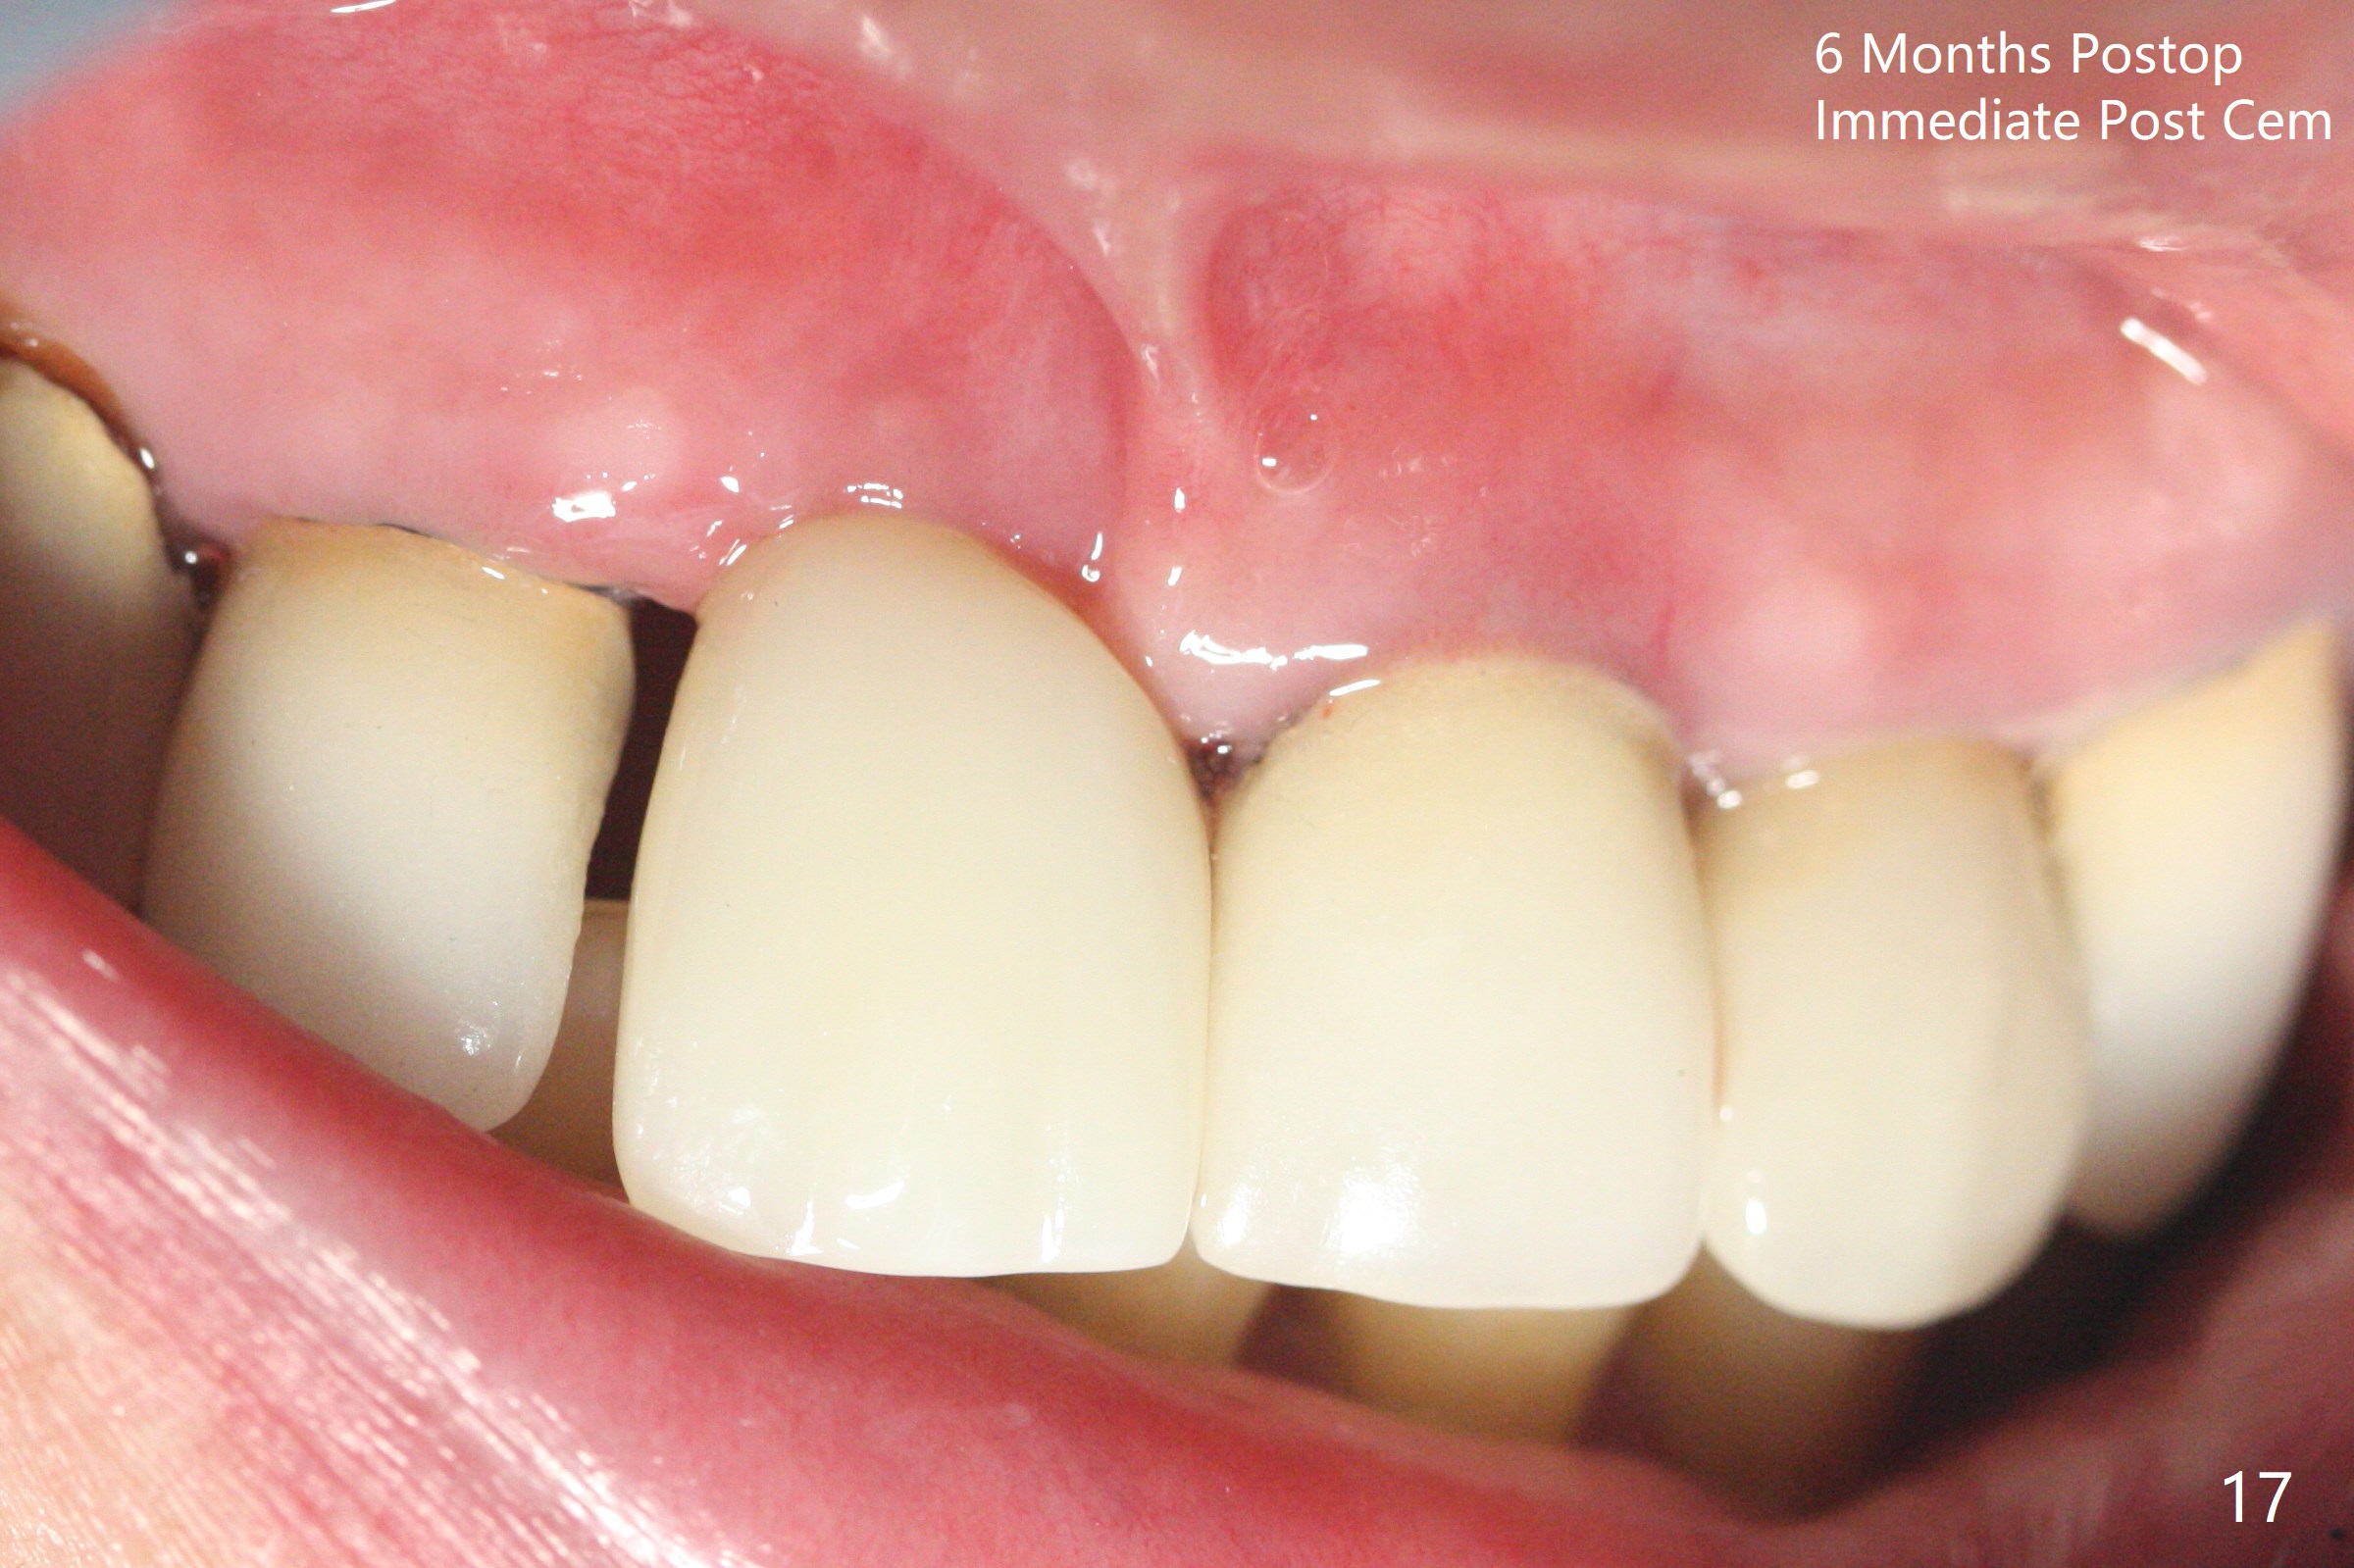

徒手初步钻洞显示方位不对(图一),重新钻洞方位尚可,好像接近鼻底(图二:红线);植入3x11.5毫米一段式植体(图三),3-5个螺纹暴露,植体似乎接近鼻底;旋转植体三趟,植体仿佛卡人鼻底,扭力大约35Ncm,植入粘性骨粉(图四,五:*)前,塞入PRF膜,紧贴颊侧粘膜,促进瘘道愈合。骨粉不仅围绕植体,而且紧贴邻牙牙根(图六(第二轮植骨:overgrafting):<)。病人术后第二周开始使用水牙线,术后三周牙龈健康多了,瘘道消失(图七)。术后六周颊侧骨壁开始塌陷(图八:>),临时牙冠颊侧颈部显得隆起(*)。调整后,牙冠外形改善(图十一至十三),取模前颊侧牙龈缘有可能下降,两个中切牙龈缘可能一致。术后3.5个月骨粉形态(图十四)与术后即刻(图六)有所不同。颊侧牙龈仍红肿轻度触痛(图十五),可能因为临时牙冠不利于局部卫生,所以决定取模制作永久性牙冠。粘固时使用临时胶水,并且涂抗菌素。另外一个可能因素是颊侧骨板薄(图十六:*),细菌感染植体螺纹,永久性牙冠粘固前,拍摄CT(放置cotton roll),必要时,植骨。永久性牙冠远中有缝隙,为了预防病人后悔,使用临时性粘固剂固定(图十七)。Return to No Caries DIO 下一个病例 一段式植体边缘制备 导板与内提升 Xin Wei, DDS, PhD, MS 1st edition 12/22/2020, last revision 06/15/2021